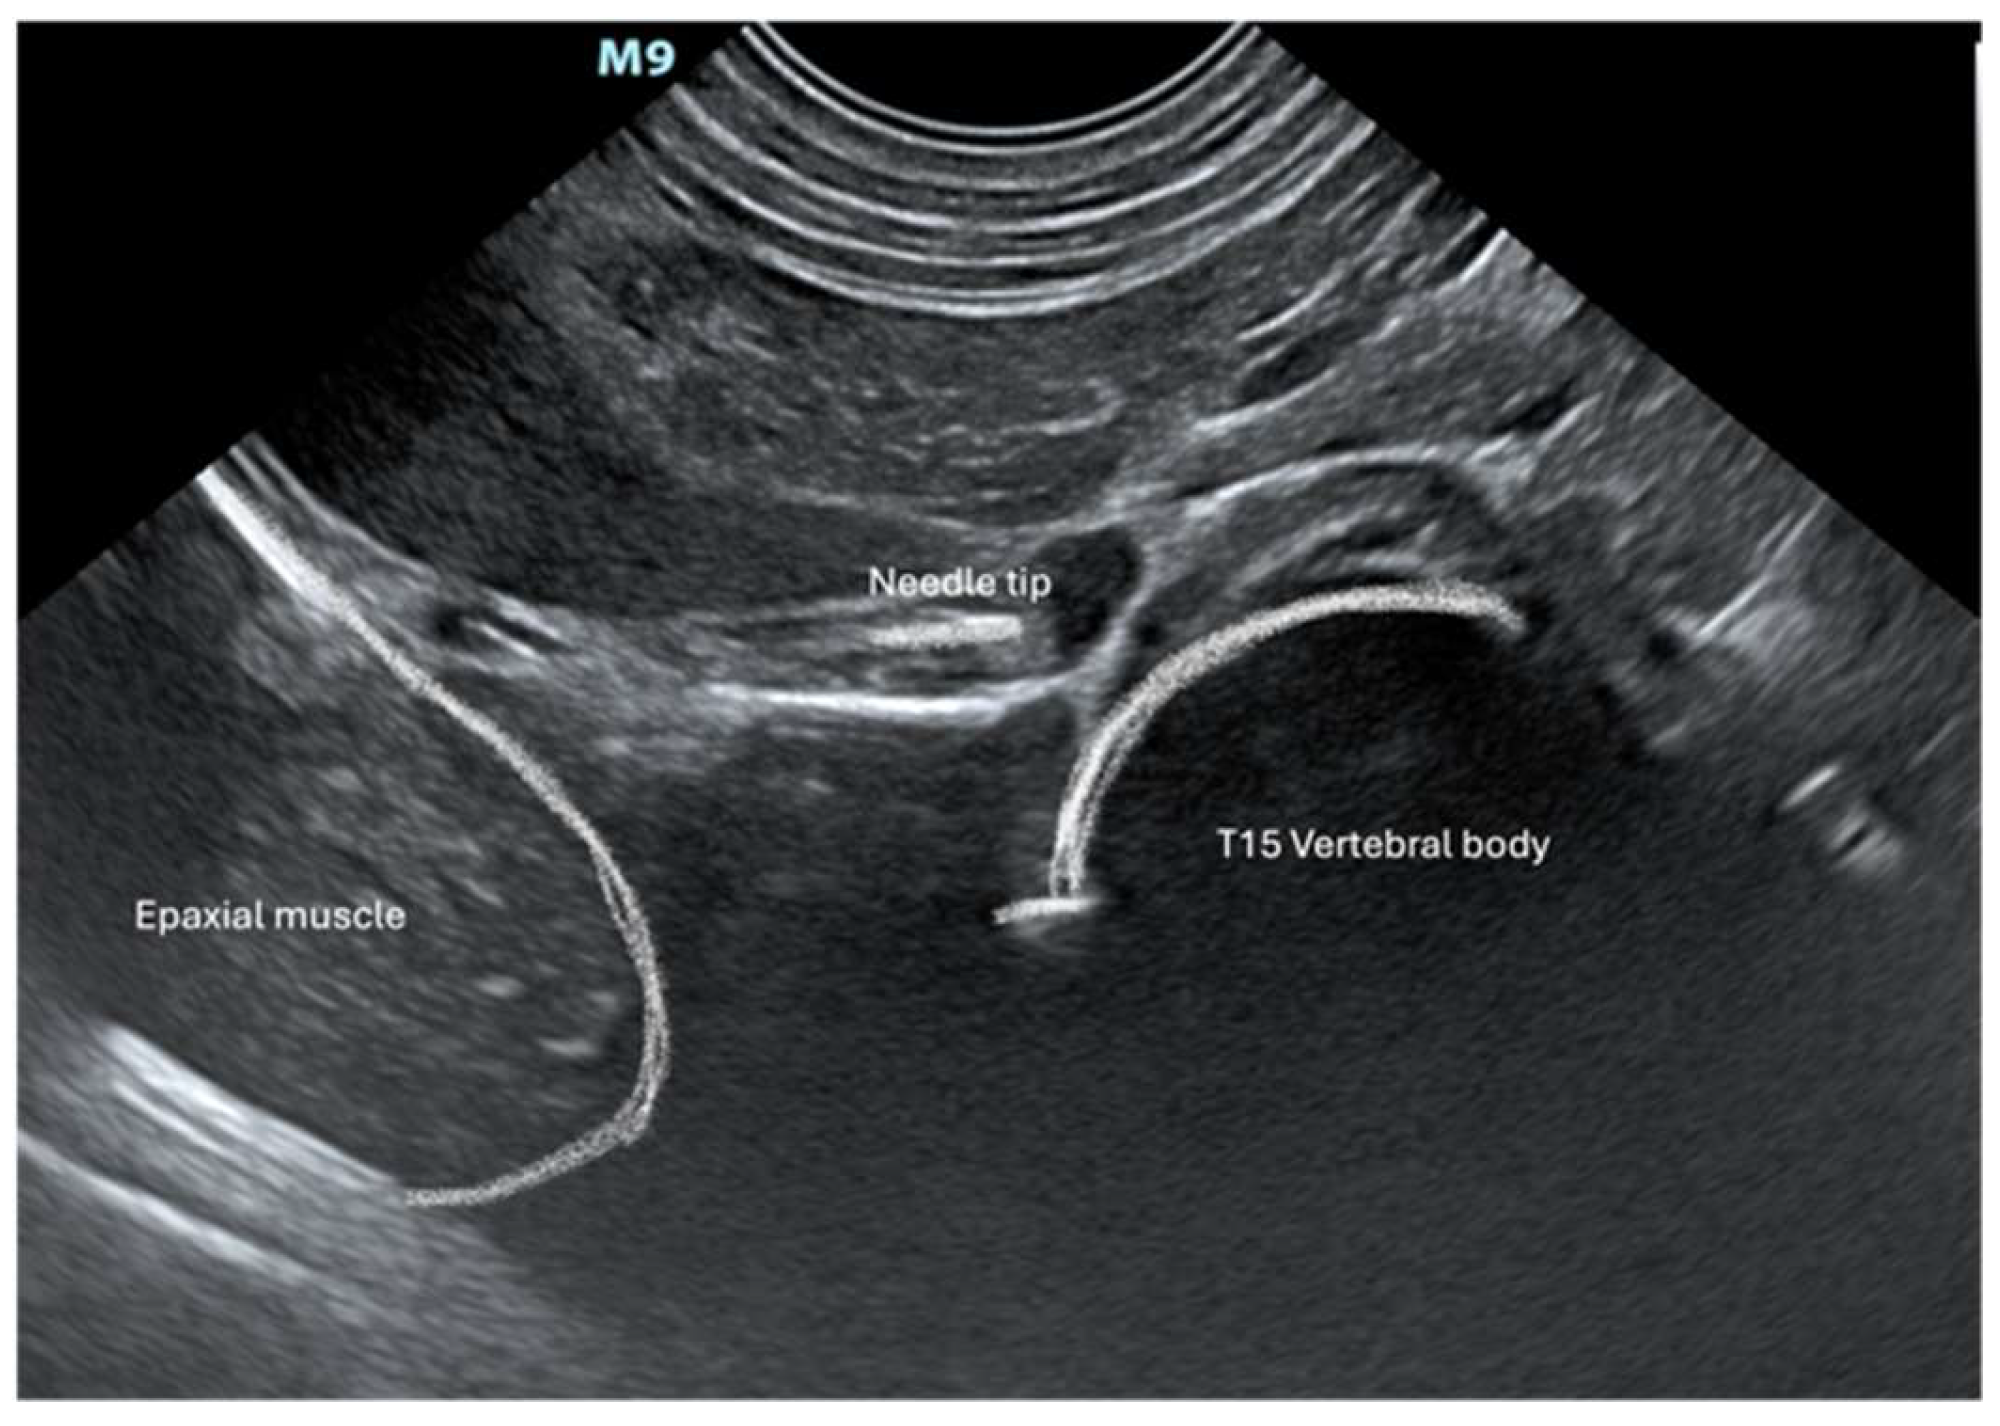

Cadavers were positioned in right lateral recumbency. A convex transducer (C11, 3s, Mindray M9 GI, Shenzhen, Guangdong, China) was placed on the craniodorsal aspect of the abdomen at the subcostal level just below the last rib (Figure 1). The transducer was gently slid and tilted to identify, in a transverse (short axis) view, the vertebral body of the last thoracic vertebra (T15). Under US guidance, an 18 G (120 mm) Tuohy needle was inserted percutaneously ventrally and parallel to the transverse process of T15 through the last intercostal space (Figure 1). The needle was advanced from dorsolateral to ventromedial through the epaxial muscle and approached the T15 vertebral body (Figure 2). Once the needle tip was in proximity to the lateral aspect of the T15 vertebral body, it was advanced towards the midline (Figure 3). Once the position of the needle was considered appropriate and no resistance to injection was felt, 2 mL of dye (China Ink, Pelikan Drawing Ink, Hanover, Germany) was applied.

Figure 3. Needle positing prior to injection of dye. The yellow dot represents the CP.